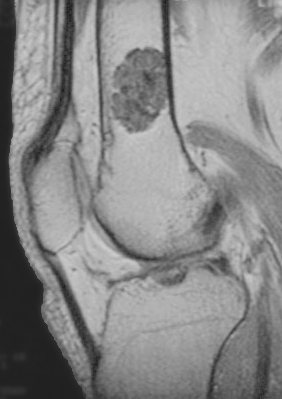

ورم غضروفي باطن (Q4613285)

| الإنجليزية | Enchondroma |

image الإنجليزية